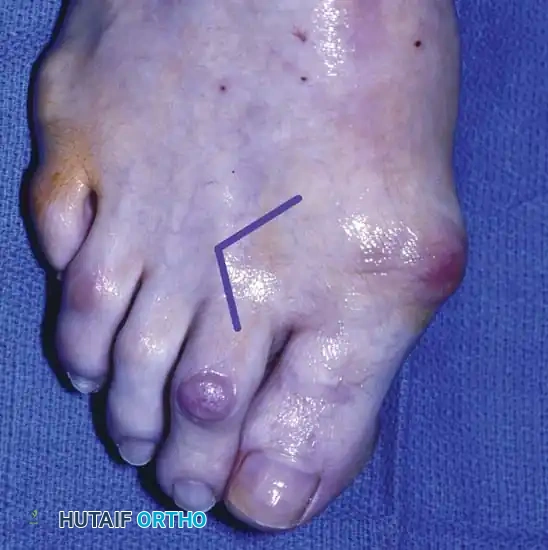

SURGICAL MANAGEMENT: HARD CORNS

Because the most common location of a hard corn is over the dorsolateral side of the PIP joint of the fifth toe, the procedure for this location is described below; however, the principles apply to all lesser toes. Coughlin and Kennedy reported the treatment of 31 lateral fifth toe corns with lateral condylectomy and flexor tenotomy, or complete condylectomy (hammer toe repair) for more severe deformities, yielding 97% good or excellent subjective ratings.

🔪 Surgical Technique 80-8: Resection Arthroplasty for Hard Corns

• Anesthesia and Positioning: Administer a digital block using local anesthesia. Apply a sterile digital tourniquet at the base of the toe.

• Incision: Make a dorsolateral incision skirting the medial border of the corn. Begin 5 to 6 mm proximal to the nail fold and extend proximally for approximately 1.5 cm.

• Exposure: Deepen the incision through the subcutaneous tissue, taking care to protect the dorsal cutaneous nerves. Retract the extensor tendon medially to expose the PIP joint capsule.

• Bone Resection: Remove the bony prominence on the dorsolateral aspect of the condyle of the proximal phalanx by sharp dissection with a small-blade knife. Using a rongeur or a small sagittal saw, resect any bony prominence from the adjacent side of the middle phalangeal base.

• Assessment of Resection: Palpation of this area after removing the prominence is far more revealing than visual inspection. Ensure that absolutely no bony prominence remains. If necessary, resect the entire head and neck of the proximal phalanx.

• Complete Resection (Hammer Toe Repair): Resection of the head and neck of the proximal phalanx more reliably prevents recurrence and is the most commonly utilized procedure for rigid deformities. While this creates instability at the resected PIP joint, this annoyance is mitigated by appropriate postoperative taping.